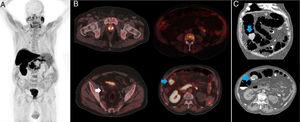

A 74-year-old man had a history of hormone-resistant, locally advanced prostate cancer. He was referred to our service due to suspicion of locoregional recurrence suggested in the control computed tomography (CT) scan that showed vesical trigone and left seminal vesicle involvement. Compromise was more doubtful at the level of 2 right pelvic regional lymph node chains. An 18F-choline PET/CT study was ordered for restaging (Fig. 1A and B) and identified a hypermetabolic prostate gland, along with metabolically positive right pararectal and external iliac adenopathies (white arrow), suggestive of malignancy, and also identified spinal bone infiltration. In addition, the imaging study showed hypermetabolic parietal thickening (30 mm) at the hepatic flexure (blue arrow), with a maximum standard uptake value (SUV) of 11.4, thus ruling out malignancy. Given the diagnosis of low-grade dysplastic villous adenoma made from the colonoscopic biopsy (Fig. 1C), right hemicolectomy was performed, revealing a well-differentiated, infiltrating adenocarcinoma (G1) that extended to the submucosa (pT1), under the villous adenoma. In the present case, 18F-choline PET/CT enabled the complete restaging of the prostatic lesion, as well as the location and diagnosis of a previously unsuspected neoplasm.